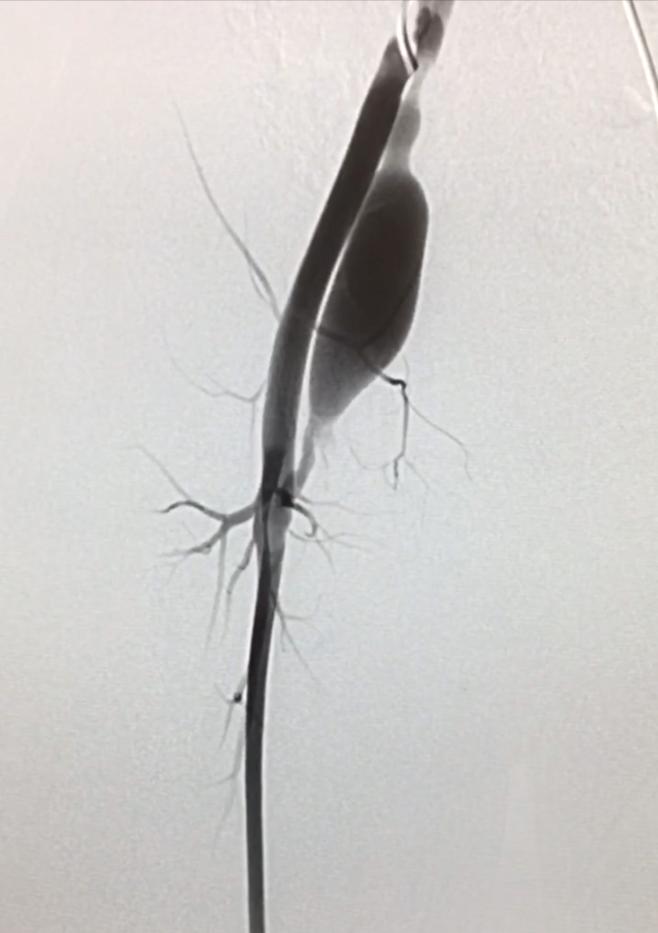

和家长沟通确定治疗方案后,孩子全麻下,穿刺股动脉,把导管置入右下肢血管行造影,术中造影看到特别明确的股动静脉瘘,瘘道长度及宽度和术前评估相似,决定弹簧圈栓塞,没想到困难重重,动脉端难超选,角度太小,母管固定难,小的弹簧圈站不住,无法成圈,大弹簧圈稍长又脱出。

介入术中造影可见瘘口,弹簧圈栓塞后消失